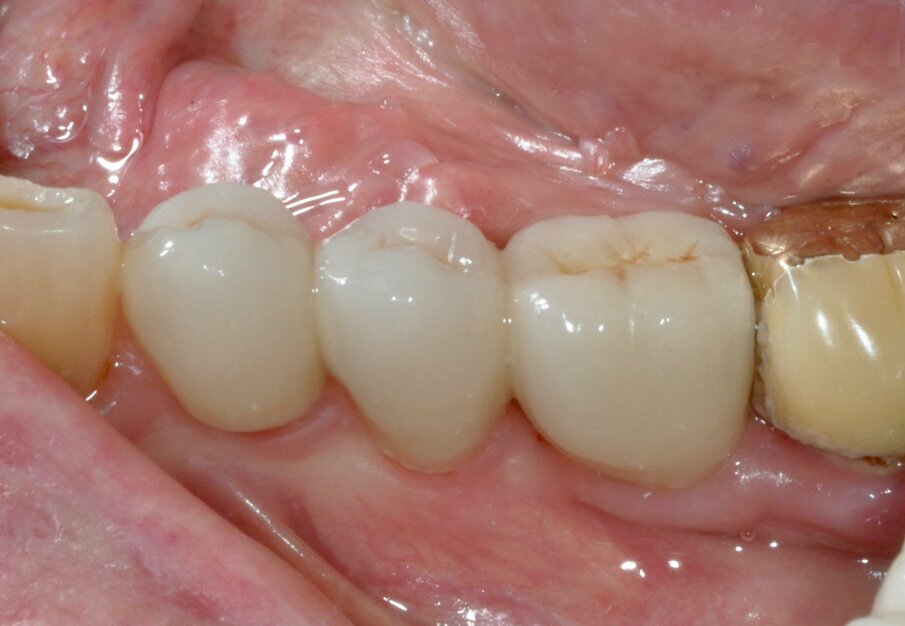

After nine years, a new radiograph was performed which highlighted how the scallop had not only been maintained but even remodelled (Figs. 7a & b). The supra-implant bone appearance around the abutments presented a hyperdense and extreme continuity with the abutment neck, despite the non-punctual hygienic maintenance, highlighted by the state of the soft tissue and by the caries affecting tooth #37, then in the terminal stage (Figs. 8 & 9). After removal of the bridge, we tried probing, but it was absolutely impossible owing to the thickness of the soft tissue.